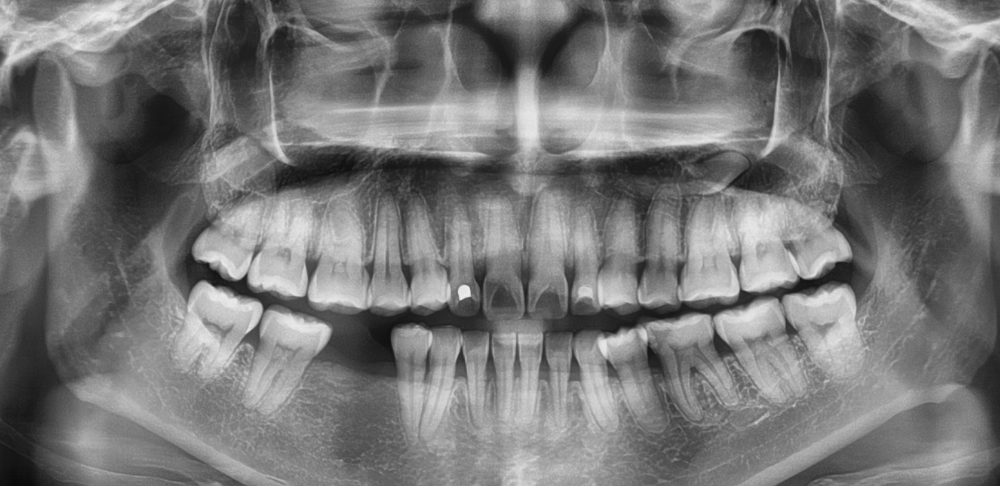

RTG pantomograficzne (panorama) daje ogólny obraz wszystkich zębów, kości szczęki i żuchwy oraz zatok szczękowych. Jest szczególnie przydatne w:

Korzystamy z cyfrowych aparatów pantomograficznych, które minimalizują dawki promieniowania i zapewniają doskonałą jakość obrazu.